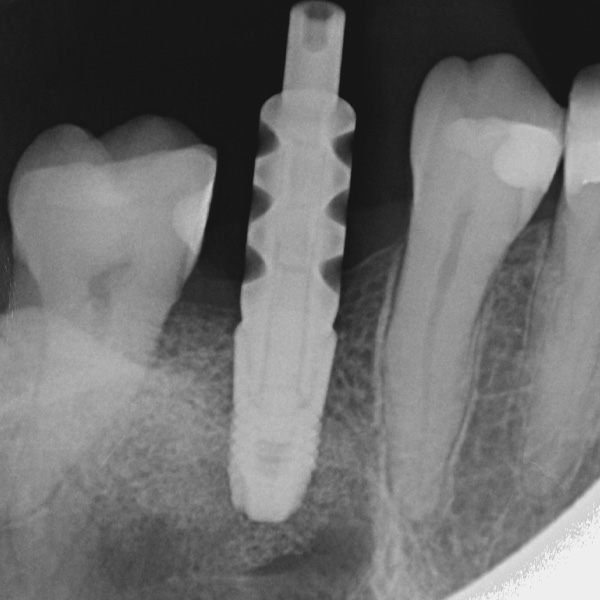

Restaurationen auf Implantaten sind besonders hohen Belastungen ausgesetzt. Da dem Patienten der elastische Faserapparat des natürlichen Zahnbetts fehlt, werden Kaukräfte nicht absorbiert, sondern direkt auf die Restauration, das Implantat, den Knochen sowie die Gegenbezahnung übertragen. Die Hybridkeramik VITA ENAMIC verfügt über eine duale Netzwerkstruktur aus Keramik und Polymer. Daraus resultieren eine dentinähnliche Elastizität und die Fähigkeit, Kaukräfte zu absorbieren. Der mehrfarbige Rohling VITA ENAMIC multiColor in der Geometrie EMC-16 ermöglicht aufgrund seiner hohen vertikalen Dimension auch bei atrophiertem Knochen die Herstellung einteiliger, monolithischer Abutmentkronen. Zahnarzt Professor Dr. Alexander Hassel zeigt im folgenden Beitrag, wie er eine Patientin mit dieser Restaurationsform versorgt.